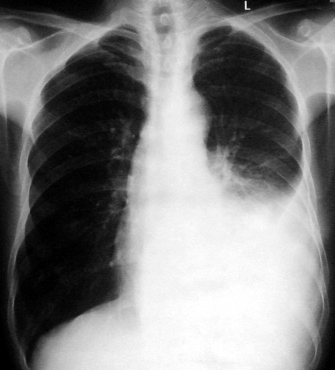

男,54岁,咳嗽,气喘半年,胸痛一月.

血性胸水

左侧胸腔积液 斜裂积液 心包积液 左肺不张 考虑左肺ca并胸膜心包转移。

支持左肺下叶中心型肺癌(累及舌叶)伴阻塞性肺炎、膨胀不全、胸腔积液、心包少量积液。

考虑左肺下叶中央型肺癌伴阻塞性肺炎及肺不张,纵隔受累可能,胸膜转移。